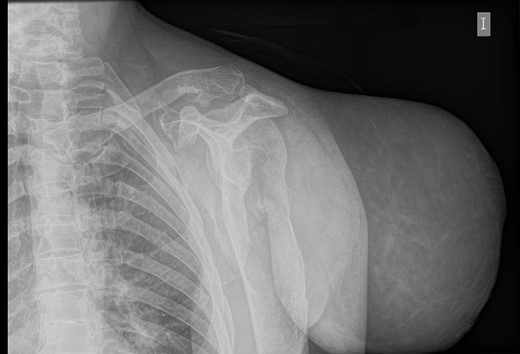

During the follow-up, a magnetic resonance (Figs 3 and 4) was performed describing a soft tissue lesion highly suggestive for liposarcoma as a first possibility diagnosis, with an addition image suggesting metastatic axillary lymph node. After the imaging results, biopsies were taken and analysed by the pathologist with a final diagnosis of PL.

Magnetic resonance imaging T1: polylobulated lesion with multiple septa separating different areas of fat tissue.